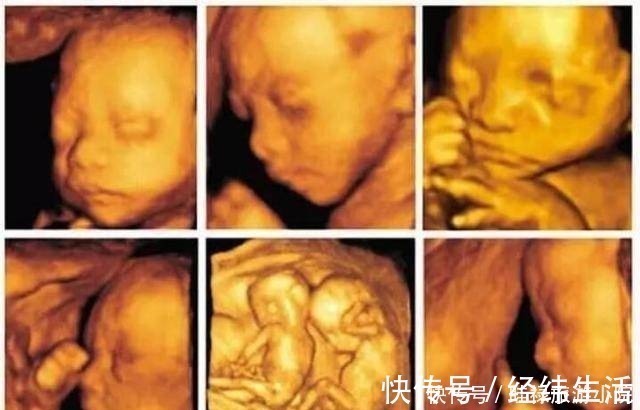

检查时间:怀孕中期,一般在孕24周时检查。现在不少医院大排畸检查,直接做四维B超,会看的更清楚些。排畸检查是孕期最系统的胎儿发育情况的检查,除了检查胎儿的外表可能存在的畸形外,也会检查胎儿内脏的发育情况等。